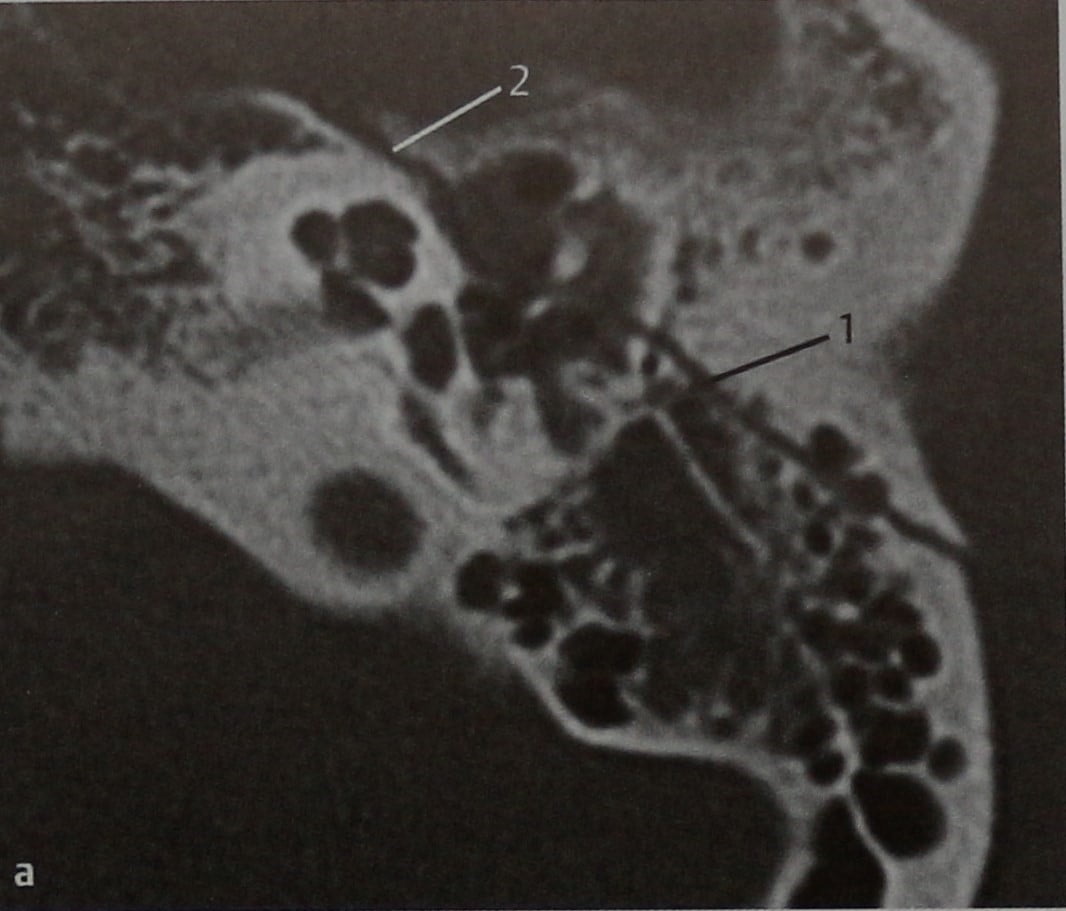

КТ анатомия сосцевидного отростка: особенности и показания